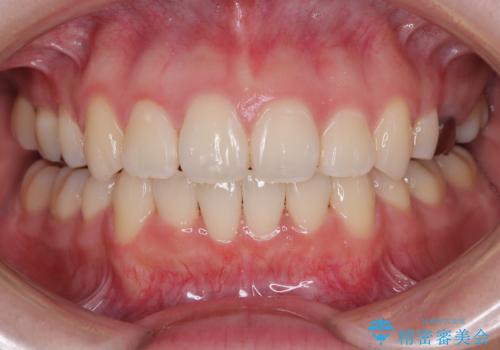

口元の突出感を改善したい。リンガルアーチを併用した抜歯矯正

上下の保定用マウスピースの他に、デコボコの強かった下顎前歯にはワイヤーで保定をしています。